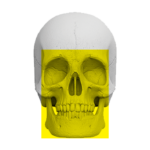

Zakres pracy tomografu.

(Badanie CBCT)

Twarzoczaszka

( 16 cm x 17 cm )

Zatoki przynosowe

( 16 cm x 17 cm )

Piramidy kości skroniowych

( 16 cm x 6 cm )